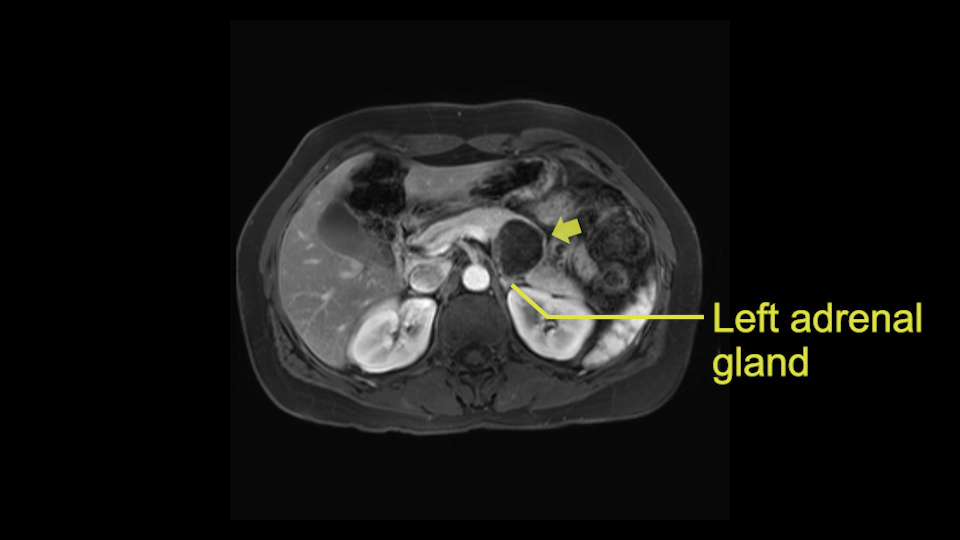

Tumor proximity to left adrenal gland

The lesion also is quite posterior. While the plane between the cyst and the left adrenal gland is often preserved, we do have to pay attention here so that we remain in the right plane and maintain our margin here. Occasionally in these cases, en bloc adrenalectomy needs to be performed.

Sometimes with even benign lesions of the spleen you can have quite a lot of inflammation in the retroperitoneum and so I do think about and wonder whether I will have some difficulty in the retroperitoneum and I usually look at the scan for that purpose. It looks like there is no inflammation in the retroperitoneum. It does look very close to the patient’s left adrenal gland but knowing the planes and suspecting that there isn’t any active inflammation, this should be able to come off the left adrenal gland without any difficulty. But obviously prepared to take some of the left adrenal if that’s necessary in this procedure. So those are my procedure-specific slowing down moments in a distal pancreatectomy when I’m considering a laparoscopic approach. I think the patient-specific slowing down moments in this particular case I have discussed with the procedure-specific moments. I don’t really see any other issue or that I have to be careful of or consider.

Proximity of lesion to splenic vein, left adrenal gland, bowel loop

Distance from surrounding structures (left adrenal gland, bowel) and vessels

So first, I'll show you the scan. Here's the traditional view, where you see the cyst, which is in the body of the pancreas. And you see over here, it's got a quite thick wall. And going a little bit back also, here you see a septation which is very important, because I think a septation is what separates this from, for instance, the pseudocyst of the pancreatitis. And also the location of the cyst you see here, abutting the adrenal gland and going down a bit more, it's also quite close to a bowel loop. So when thinking about this cyst: female, the location in the body of the pancreas, thick wall, septation, and as you can read in history, it was basically asymptomatic, so no signs of pancreatitis. So, this probably all points towards a mucinous cystic neoplasm.

So what I would normally do in these patients, I would look at the abutment of any other organs, one, which is here, potentially the adrenal gland and two the small bowel. And two, look at the distance from the vessels which I would normally do in a coronal view. So you can easily measure the distance and third I look at the insertion of the inferior mesenteric vein. Now we can probably also see that on here. Although it's better on a CT scan and it's better on a coronal view, you want to know where the inferior mesenteric vein comes into either the splenic or the SMV, because that is typically a very important slow down moment when you mobilize the lower portion of the pancreas knowing where the inferior mesenteric vein comes in either the splenic vein or the SMV. So those are I think the three most important points for the CT scan.

After you've slung the pancreas, to the left of the cyst, and if you encounter any adrenal involvement later after you have transected the pancreas and you move to the left side of the patient towards the spleen, take either the entire or partial left adrenal gland with the resection. If you go underneath the adrenal gland, and it's probably best to do a full RAMPS (Radical Antegrade Modular Pancreatosplenectomy) procedure, that is where you take the Gerota’s fascia completely onto the mucinous cyst. And that's very crucial to get a radical resection if you think the adrenal gland is involved.